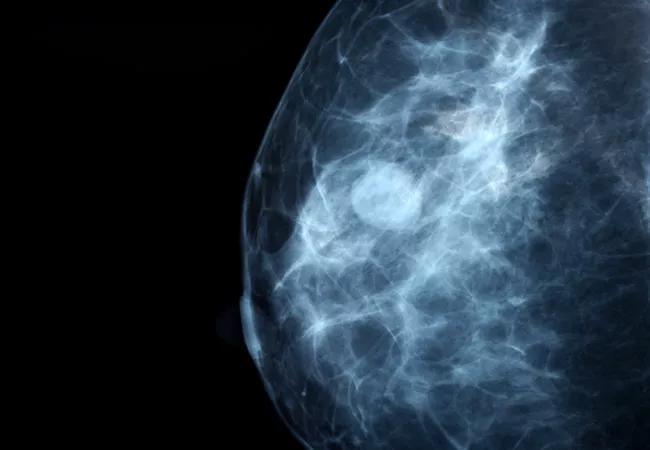

Q. Should We Treat All Breast Cancer Aggressively, Just to be Safe?

A. All patients don’t need all treatments. As our knowledge and understanding of outcomes has improved, we can safely personalize care. Using evidence-based management practices, we often are able to provide the best results with less treatment and minimal side effects.

Studies have shown that some patients over age 65 with early-stage breast cancer may be safely managed with surgery alone and may not need chemotherapy or radiation. In fact, radiation has not been shown to improve long-term survival in these patients

Similarly, chemotherapy is no longer prescribed for certain stages and types of breast cancer. We use molecular tests to determine which patients will and won’t benefit from chemotherapy.

For some patients when radiation is warranted, a single dose of intraoperative radiation can lower recurrence risk in a cost-effective way without causing side effects.

Because prognostic information based on molecular type allows us to personalize care, we engage patients in discussions of benefit and risk. They need to know that aggressive treatment may not always mean better outcomes.